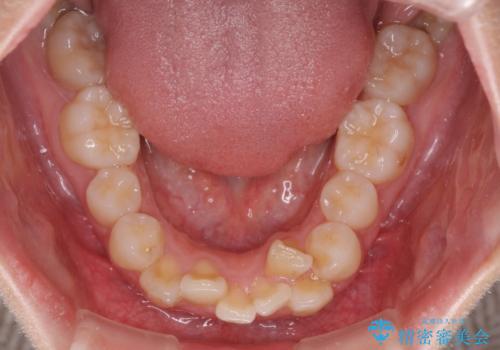

- 前に傾斜して飛び出した上顎前歯を気にして来院された患者様です。

上下前歯の前後差が大きく、下顎前歯が隠れるほど深い咬合で、咬合力が強い状態でした。

口元の突出感を改善するために、上下左右の第一小臼歯4本を抜歯し、ワイヤー装置にて矯正治療を行うこととしました。